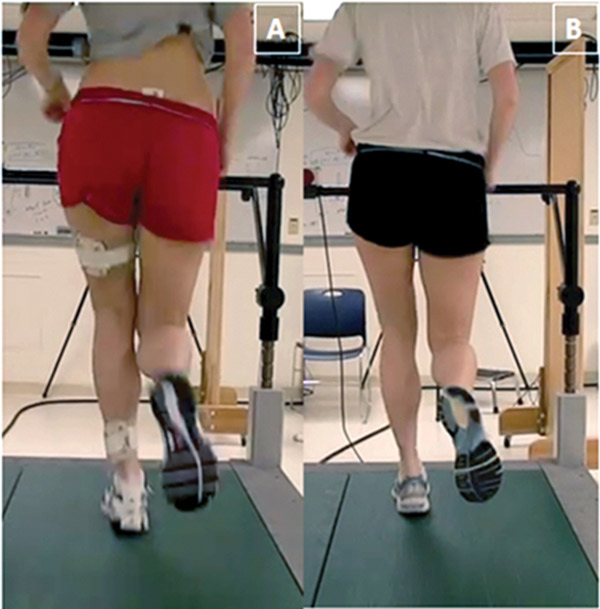

این موضوع میتواند به مشکلاتی در مکانیک بدن در حین دویدن و وضعیت بدن مرتبط باشد. جان شیلکوفسکی، فیزیوتراپیست آمریکایی توضیح میدهد: «وقتی نقص در قدرت یا موبیلیتی وجود داشته باشد، میتواند منجر به تغییر الگوهای حرکتی (مانند افتادگی لگن) یا عدم تقارن شود. این امر باعث افزایش اصطکاک بورسها در حین حرکت شده و در نهایت منجر به التهاب و تورم بورس میشود.»

ضعف عضلات ابداکتور (دورکننده) لگن نیز یک مقصر رایج است. نقش این عضلات، دورکردن پاها از مرکز بدن است و باعث میشوند لگن شما هنگام دویدن تثبیت شود. اگر ابداکتورها ضعیف باشند، منجر به حرکت بیش از حد در لگن میشود که فشار اضافی به لگن، کمر و عضلات اطراف آن ناحیه وارد میکند و در نتیجه باعث افزایش اصطکاک بورسها میگردد. خشکی در ناحیه کمر (که موبیلیتی را محدود میکند) و همچنین پرونیشن بیش از حد (چرخش مچ پا به داخل) که فشار اضافی به لگن وارد میکند نیز میتوانند مقصر باشند.

علاوه بر زیادهروی در تمرین، عواملی مانند ضعف عضلات ابداکتور (دورکننده) لگن، کاهش موبیلیتی و پرونیشن بیش از حد مچ پا (چرخش به داخل) و افتادگی لگن، باعث افزایش اصطکاک بورس و التهاب آن میشوند.